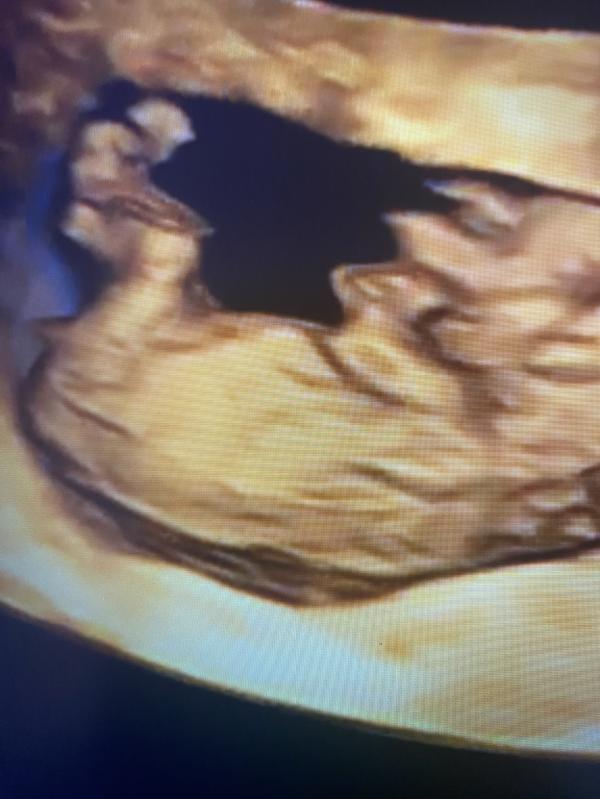

2-ой скрининг.

Слава Богу, всё в порядке.

Девочки, через неделю скрининг, где узнаем пол малыша. Предлагаю пока погадать, кто у нас) сделала фото с видео, где видно бугорок. Сама я в этом не бум-бум.